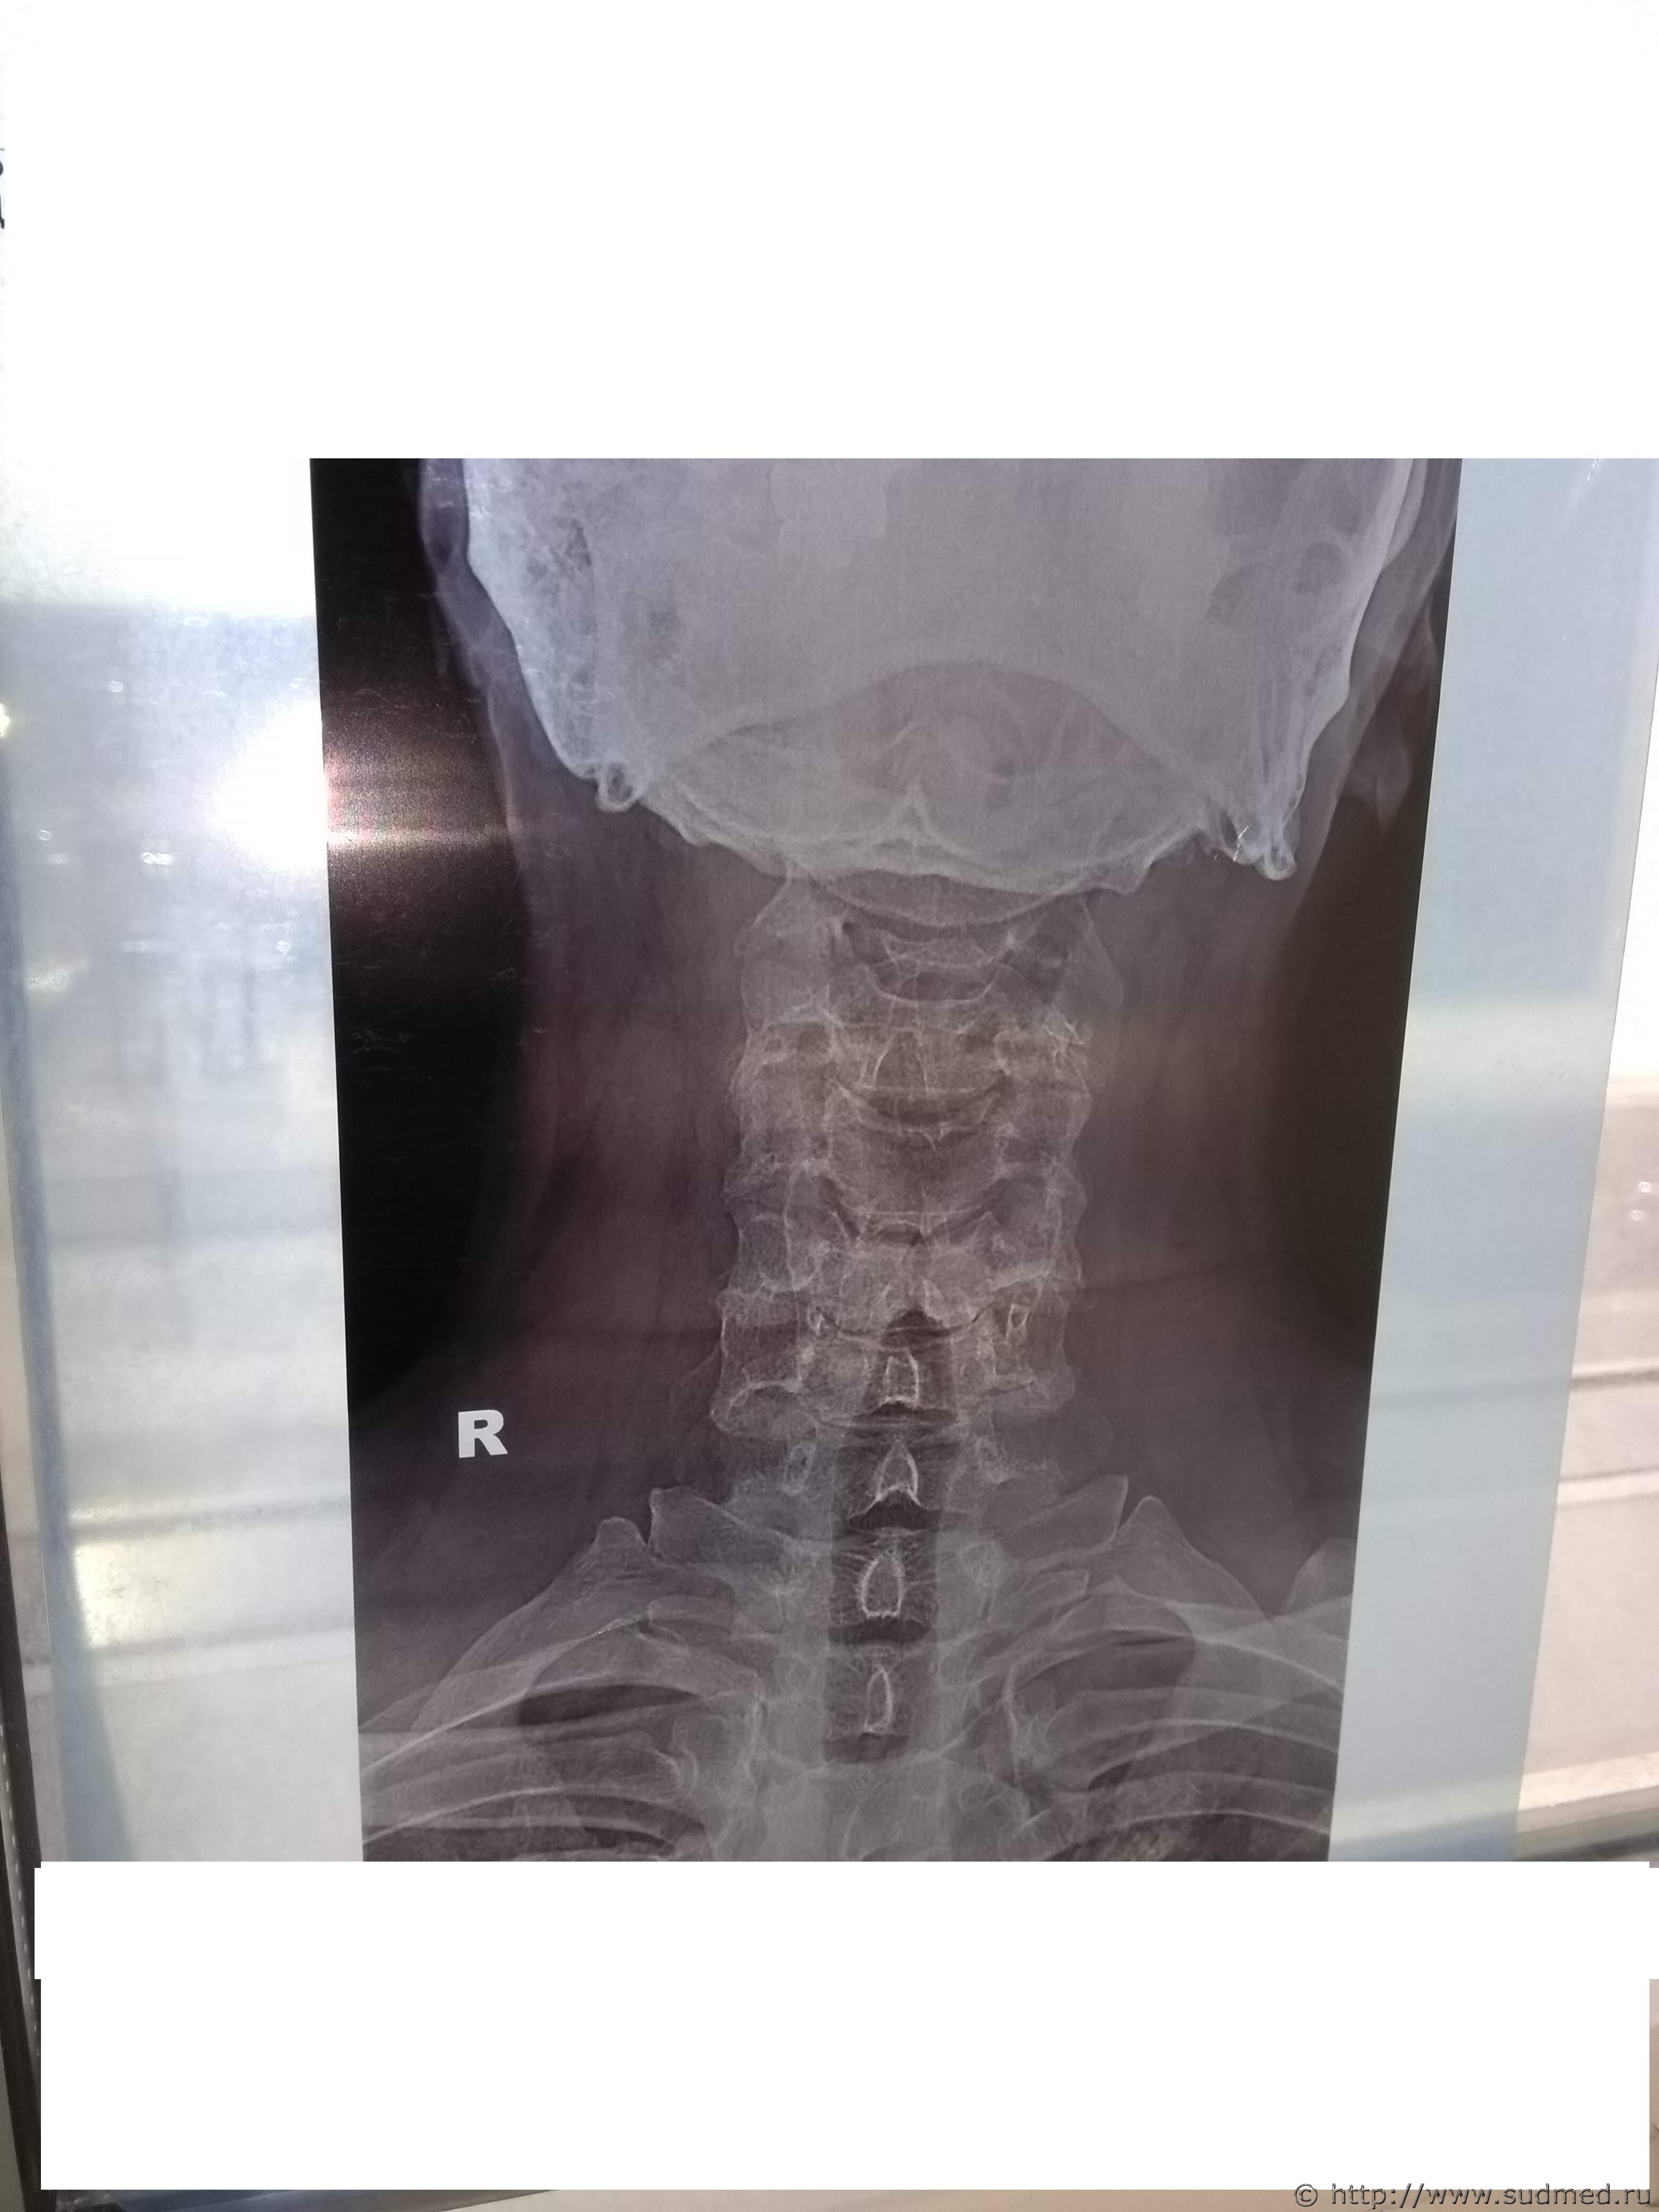

Какие повреждения видны на этой фототаблице?

Похоже на перелом щитовидного хряща, но утверждать не берусь: качество изображений низкое.

А мне кажется там компрессионный 5-6-го, либо перенесенный в анамнезе.

Между тем врач рентгенолог на суде сказал:

1. Снимок сделан для исследования костных структур шеи. Объясняется тем, что в центре снимка находится позвоночник, а не гортань. У рентгеновского аппарата два режима, один для исследования костных структур, второй для исследования мягких тканей.

2. На рентгеновском снимке не видно щитовидного хряща. Т.е. получается как в одном фильме. Ты суслика видишь. Нет. А он здесь есть.